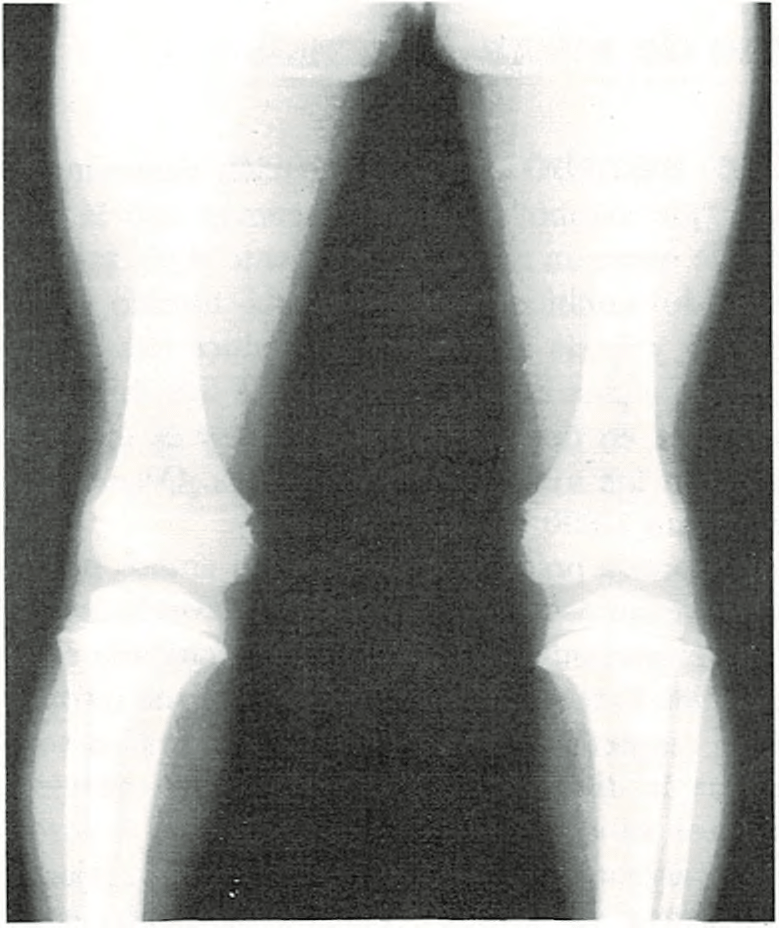

Piernas arqueadas.

Casi todos los recién nacidos parecen tener las piernas curvas. Las rodillas

se hallan dirigidas hacia fuera y los pies ligeramente vueltos hacia dentro. A pesar de que los huesos generalmente están bien formados, las piernas tienden a seguir adoptando la posición que tenían en el claustro materno.

Las piernas curvas no desaparecen en el niño hasta al cabo de un cierto tiempo de caminar. Deben enderezarse primero el tobillo y los músculos del pie, así como los músculos y ligamentos de sus piernas y rodillas. A medida que los músculos se fortalecen al andar, las piernas van apareciendo más rectas y las rodillas más juntas. La edad media en la cual desaparece la incurvación de las piernas es entre 1 y 2 años.

Si tiene las piernas excesivamente incurvadas o si a los dos años no se han enderezado, se consultará al médico.

En algunos casos, las piernas incurvadas pueden estar provocadas por un raquitismo, producido por deficiencia alimenticia de vitamina D. Sólo raramente será necesario un tratamiento especial con ortopedia o cirugía.